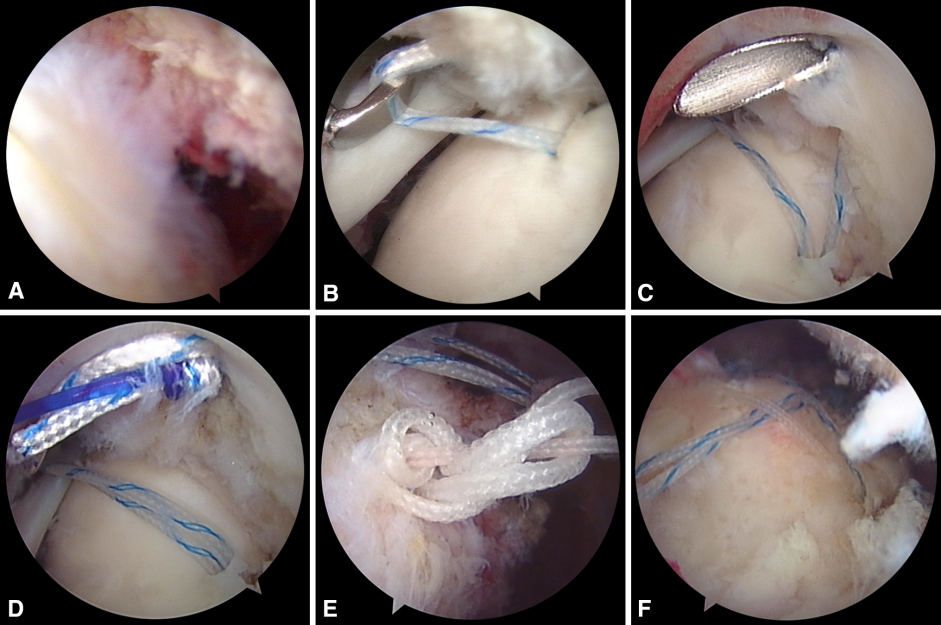

目前常用的外科技术

肱骨大结节骨折 ORIF,术前 X 线片显示肱骨大结节骨折情况;术中暴露肱

肱骨大结节骨折 ORIF,术前 X 线片显示肱骨大结节骨折情况;术中暴露肱